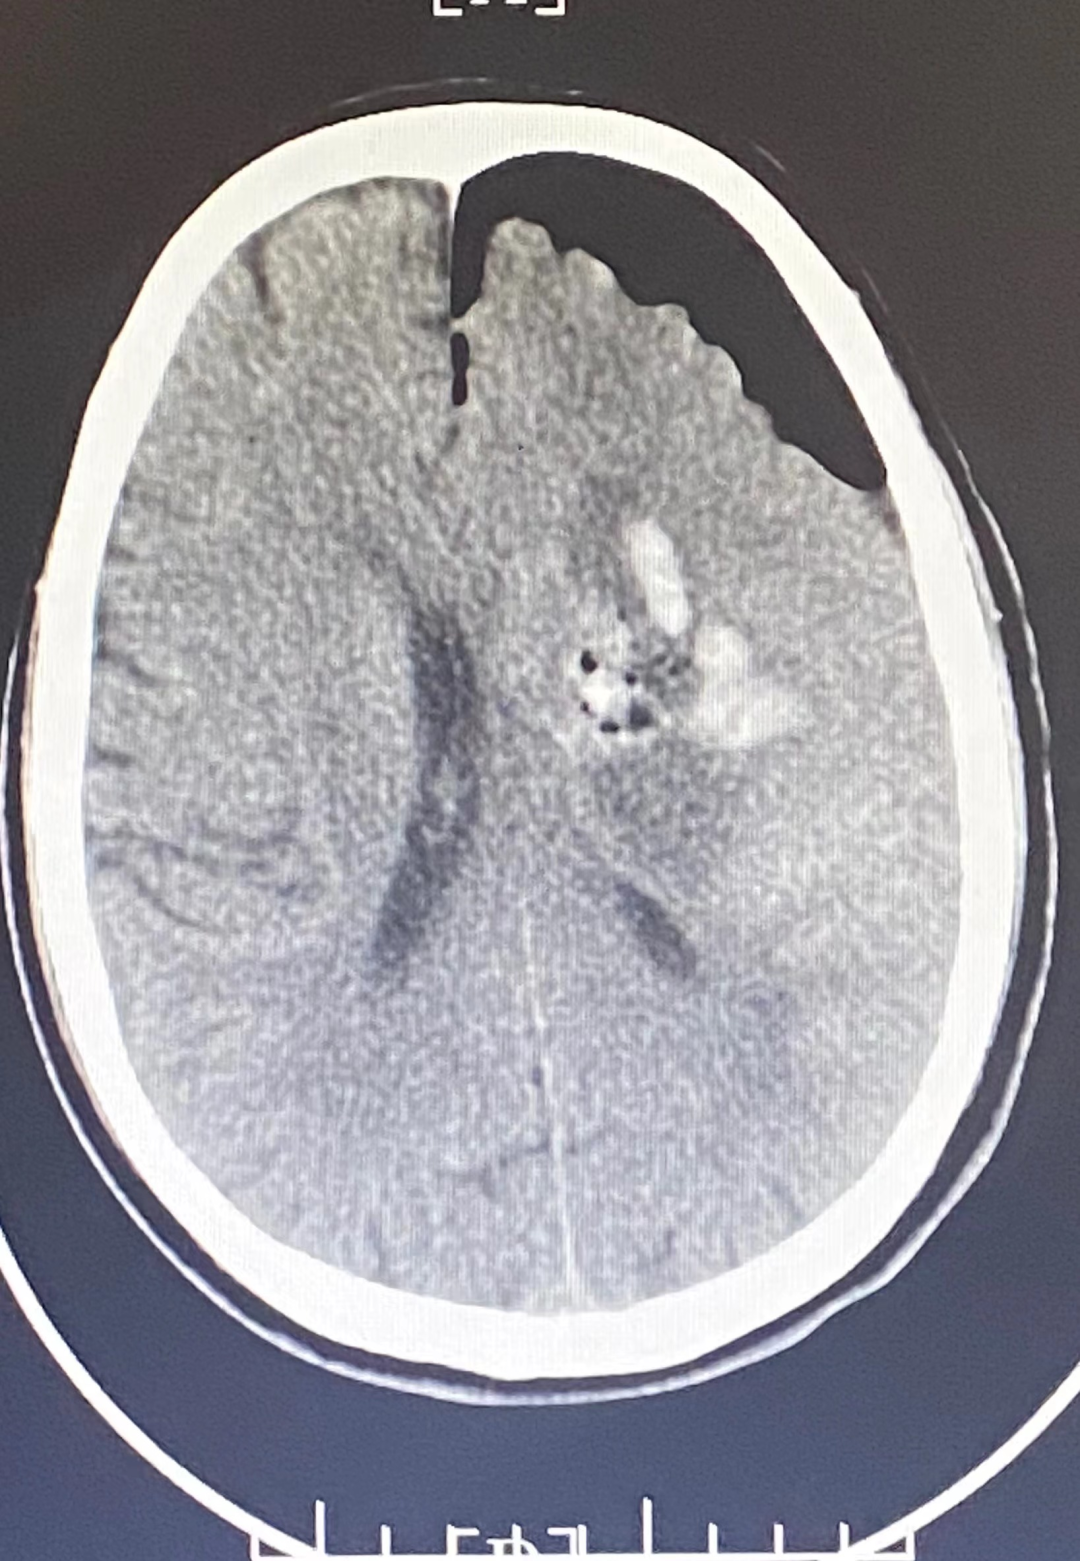

患者行神經(jīng)內(nèi)鏡下腦出血清除術,術后瞳孔等大等圓,對光反應存在。術后第1天患者神志清楚,四肢能活動,肌力正常。

圖片

手術后